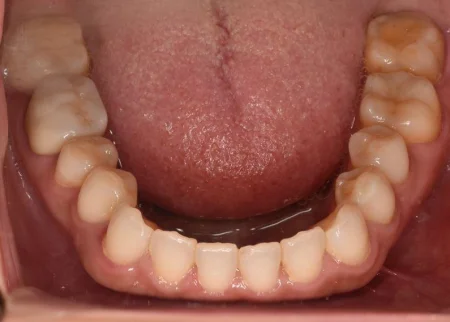

治療後

| 行ったご提案・治療内容 | 患者様のご要望通り、銀でできた詰め物と被せ物を全て取り外して、白い素材で作り直す治療の計画を立てました。 部分的な詰め物は、隣り合う歯の色味に合わせやすく自然な白さが特徴の素材である「セラミック」、被せ物はセラミックの中でも強度が高い「ジルコニア」で作製しました。 |

| 術後の経過・現在の様子 | 奥歯全体が白く美しくなり、お口を開けた時も自然で、患者様も大変満足されています。 メンテナンスに移行した現在も、月1回の頻度でクリーニングにご来院していただいています。 |